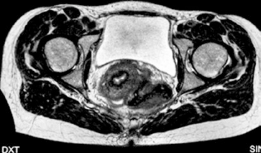

Advanced imaging with computed tomography (CT) with 3D reconstruction is increasingly utilized. 3D CT allows for precise mapping of the bony anatomy, evaluation of acetabular version, and virtual surgical planning. Magnetic resonance imaging (MRI) or MR arthrography is routinely obtained to evaluate the integrity of the labrum, articular cartilage, and ligamentum teres. Concomitant intra-articular pathology is highly prevalent in dysplastic hips and must be factored into the surgical plan, often necessitating a combined approach with hip arthroscopy or open arthrotomy.